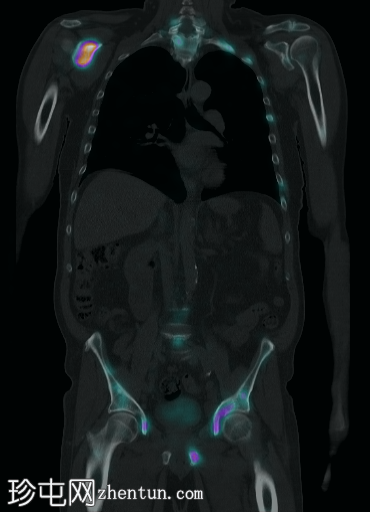

5.png

融合

MIP

脊柱、肋骨、骨盆、颅骨、肩胛骨、胸骨、左侧肱骨和双侧股骨干可见多处放射性示踪剂摄取异常增高,与SPECT-CT扫描图像上显示的硬化病灶相对应。双肾未见放射性示踪剂活性。

骨骼内多处局灶性放射性示踪剂摄取增高,符合骨转移;肾脏内无放射性示踪剂活性,与超扫描结果一致。